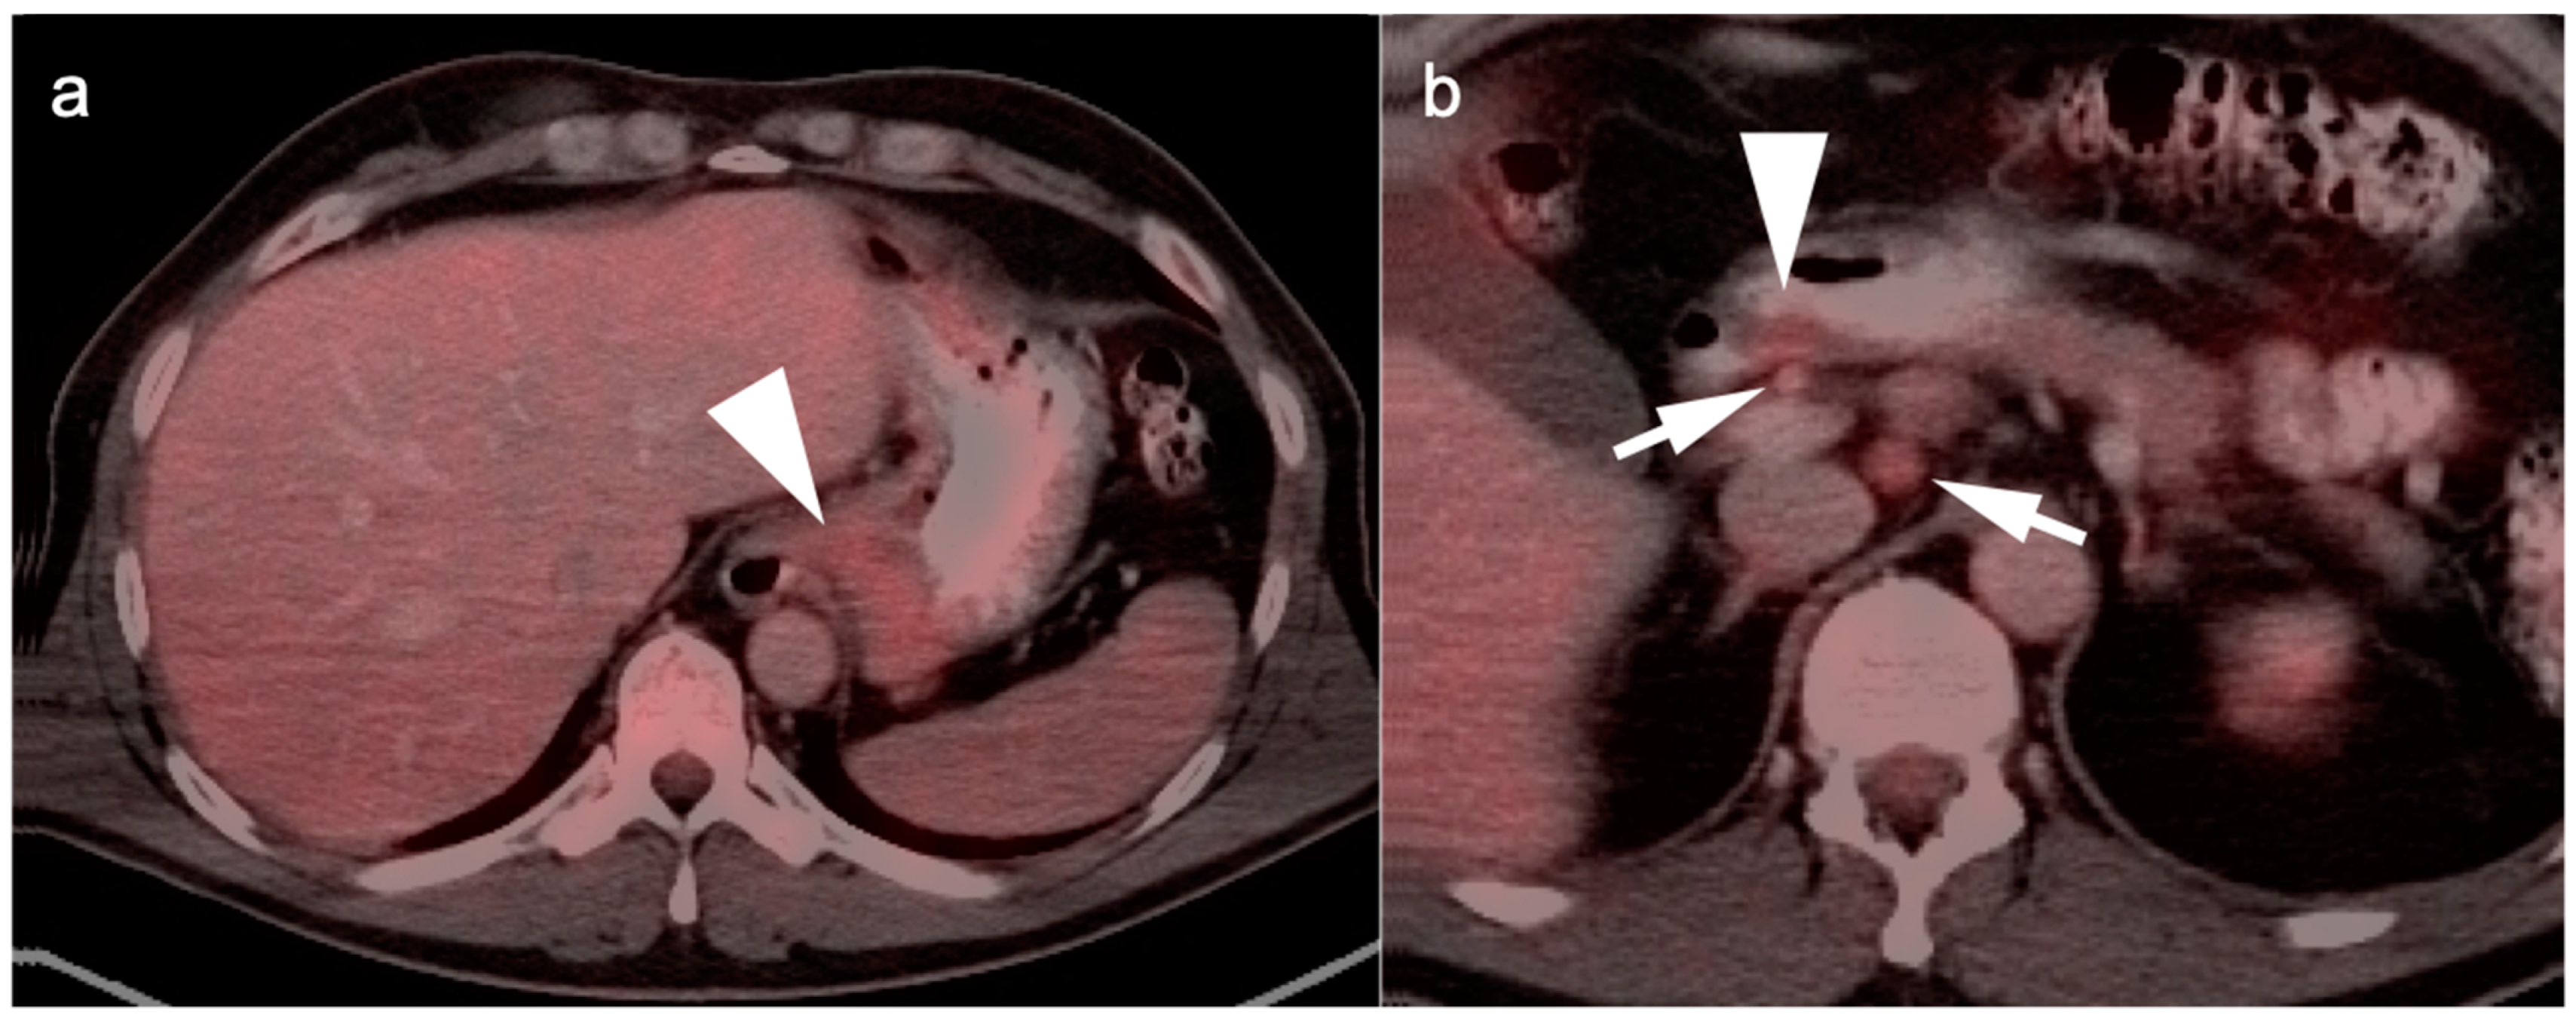

3. Gastrointestinal Stromal Tumor (GIST)